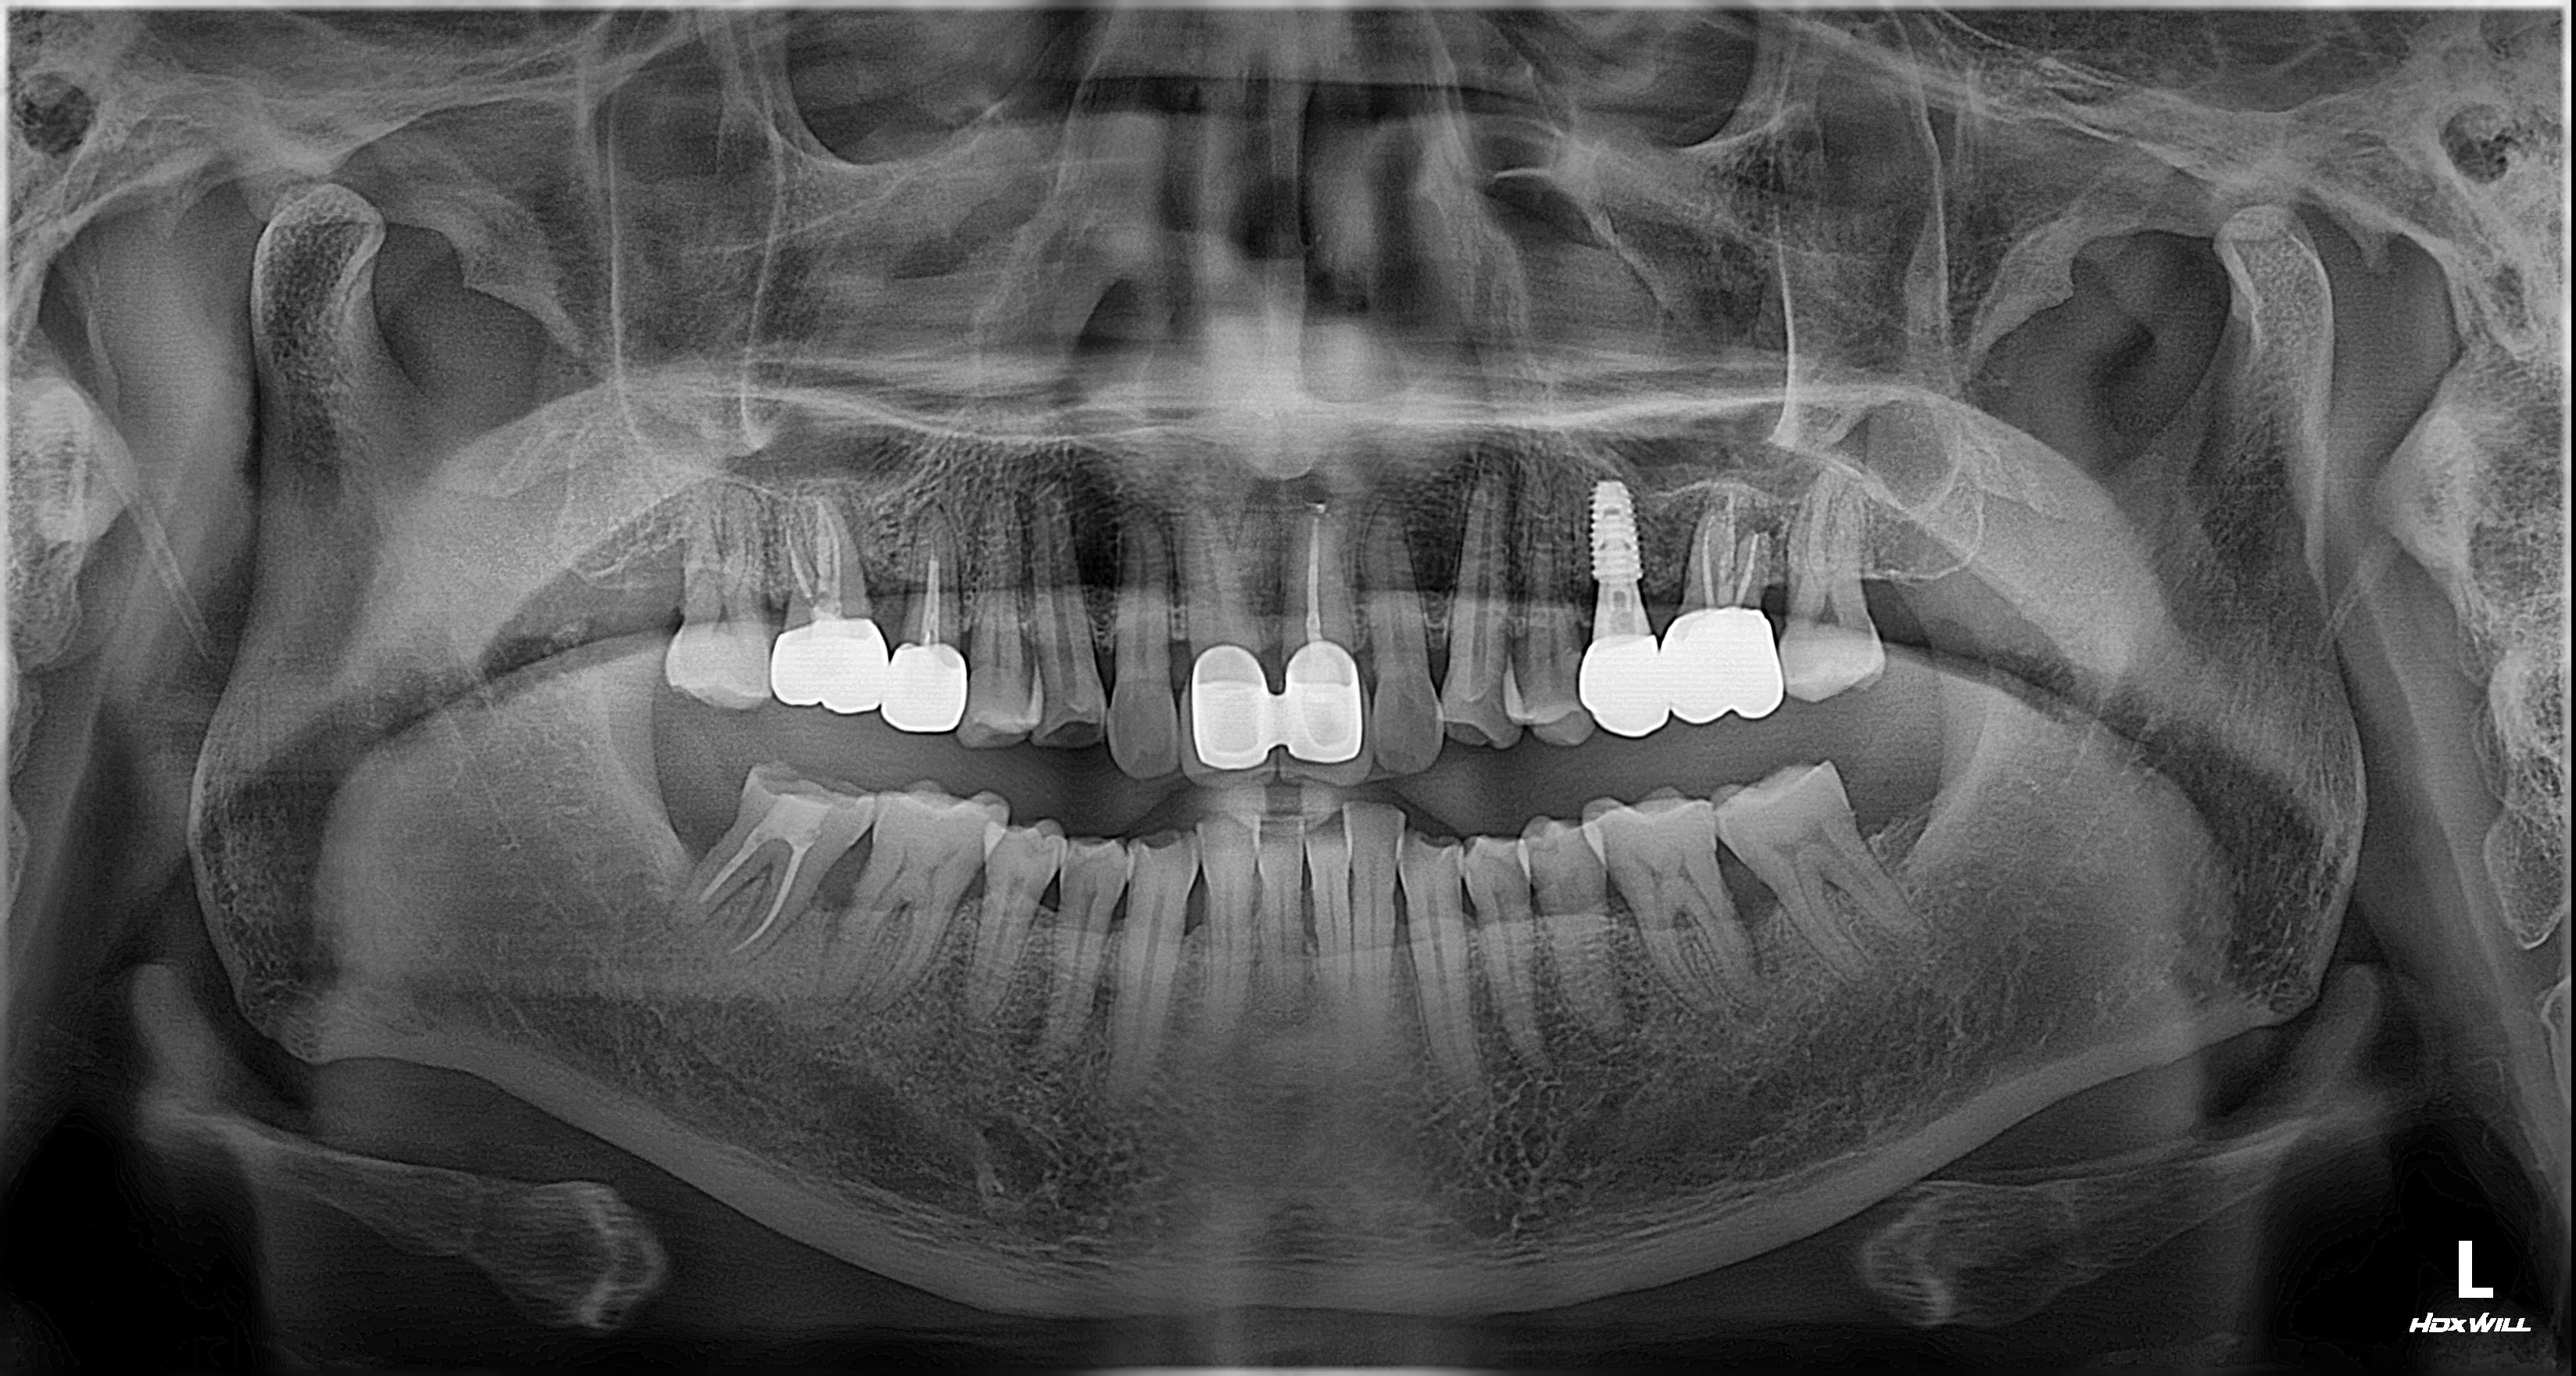

2025년 1월 20일 첫 내원 시 촬영한 파노라마 방사선 사진입니다.

진단 결과, 통증 원인은 좌측 상악 제1대구치 뿌리 끝에 발생한 심한 치근단 염증이었습니다.

치아 뿌리 끝의 염증이 주변 치조골(잇몸뼈)을 광범위하게 파괴하고 있는 상태였습니다. 자연치아 보존이 치료의 최우선 원칙이나, 이처럼 염증에 의한 골소실이 심각하게 진행된 상황에서는 신경치료나 재신경치료와 같은 보존적 접근의 예후가 극히 불량합니다.